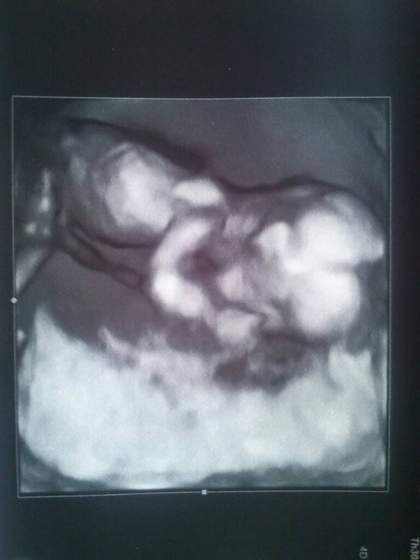

Pyta, czy chcemy znać płeć - chórem z mężem powiedzieliśmy, że tak - pokazała WIELKIEGO siurka, na zdjęciu drugim

No i ginka powiedziała, że wiadomo, na tym etapie płeć się czasem zmienia, ale ona może dać gwarancję, że się nie zmieni, bo bardzo duże i widoczne narządy

Ale kamień z serca, mamy aż 8 zdjęć, w tym dwa w 3D